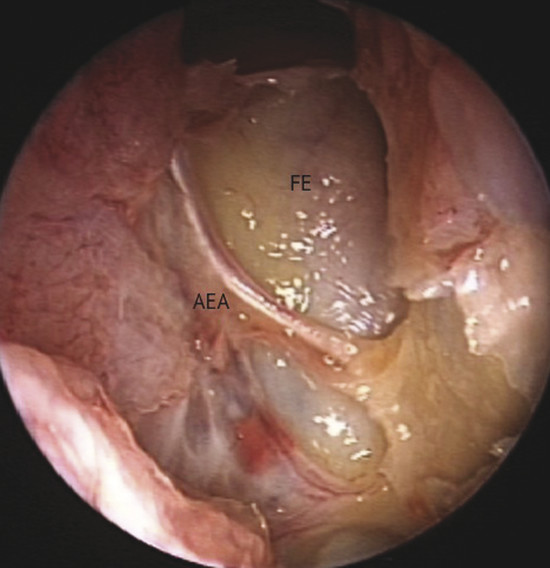

This study focused on the use of a monolateral mucosal septal flap pedicled on septal branches of the anterior ethmoidal artery (AEA), extended to the nasal floor and the inferior meatus.

Blood supply of the nasal septum occurs through septal branches of the sphenopalatine artery. Here it anastomoses with branches of the palatine and labial arteries and septal branches of the anterior and posterior ethmoidal arteries; they are easily recognizable in the cranial portion of the septum area (Fig. 13‑1). An anatomical study on the arterial pattern of the nasal septum, traced by microdissection, demonstrated that AEAs were present in all cases, but the posterior ethmoidal arteries in some cases were absent. 1 These arteries, with the middle septal branch of the sphenopalatine artery and the superior labial branch of the facial artery, mainly contribute to the anastomotic triangle of the anterior septum. Only the posterosuperior area is vascularized by the posterior ethmoidal artery branches. 2 The ethmoidal artery originates from the terminal segment of the ophthalmic artery in the orbit cavity, a collateral branch of the internal carotid artery, and passes between the superior oblique and medial rectus muscle. The AEA then reaches the frontoethmoidal suture through the anterior ethmoidal foramen and enters into the anterior ethmoidal canal along with the anterior ethmoidal nerves. The artery crosses the ethmoid roof diagonally from posterolateral to anteromedial (Fig. 13‑2). AEA then divides at the lateral part of the cribriform plate of the ethmoid, giving off two or three branches to the mucosa of the cranial portion of the septum (Fig. 13‑3). Finally, they reach the olfactory cleft and supply terminal branches to the olfactory bulb and the meninges.

Bleeding can be seen originating from a septal branch of the AEA, showing a close anatomic relation with the axilla of the middle turbinate (Fig. 13‑4). It is extremely important to consider this anatomical relation during harvesting the flap.